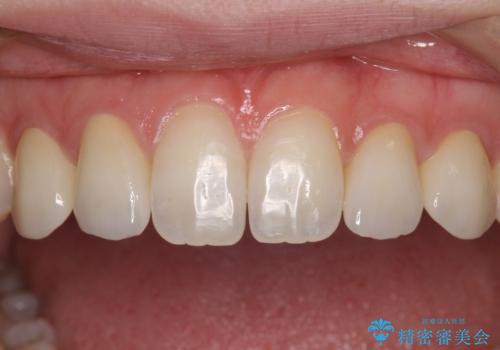

前歯の奇形歯 オールセラミッククラウンによる審美歯科治療

正中の隙間は矯正治療により閉じ、左右の4歯はオールセラミッククラウンにて補綴することとしました。

前歯2本もセラミッククラウンを装着することで隙間を閉じる治療方法もあるかと思いますが、健全な歯を削る必要は全くなく、矯正治療で対応することが望ましい治療であると考えます。